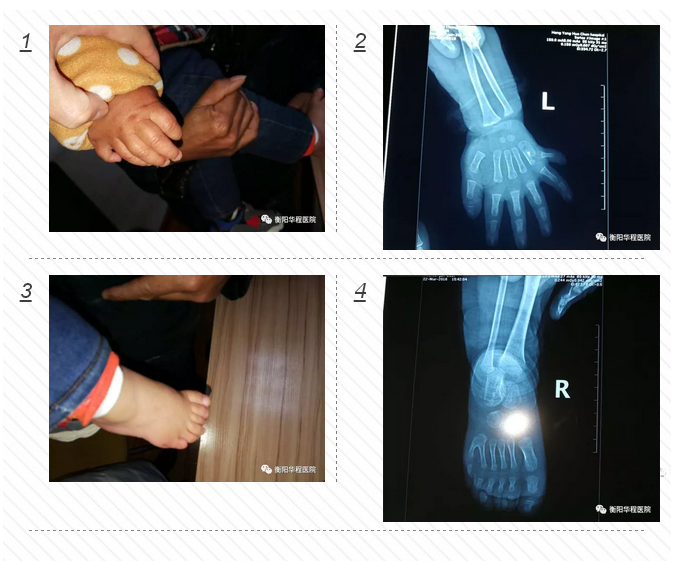

先天畸形多指 骨科醫(yī)生妙手完美手術(shù)

正常人一般只有兩個大拇指,可家住衡陽縣集兵鎮(zhèn)的1歲大的城城,雙手和雙腳比常人各多出1個小手指和1個小腳趾,不過在衡陽華程醫(yī)院骨科中心醫(yī)護(hù)人員的幫助下,3月23日下午,多出來的手指和腳趾已被成功切除。

面對這位只有1歲的小患者,骨科中心醫(yī)護(hù)人員進(jìn)行了一番細(xì)致檢查。尹治華醫(yī)生發(fā)現(xiàn)小城城的“多指”情況并不是特別復(fù)雜,突出的關(guān)節(jié)部位并沒有長出骨頭,只需切除多出的指頭,再將表皮重新縫合,扎死血管和神經(jīng)就可以了。“孩子太過幼小,血管和神經(jīng)均很纖細(xì),需借助顯微成像技術(shù)完成手術(shù)。而留下的疤痕組織也會在成長過程中逐漸減淡。”骨科中心尹治華醫(yī)生表示。3月23日小城城在全麻下行雙側(cè)多指、多趾切除功能重建術(shù),經(jīng)過一個小多小時的焦急等待,孩子平安從手術(shù)室里出來了,手術(shù)非常成功,小城城媽媽那顆懸著的心終于著了地。